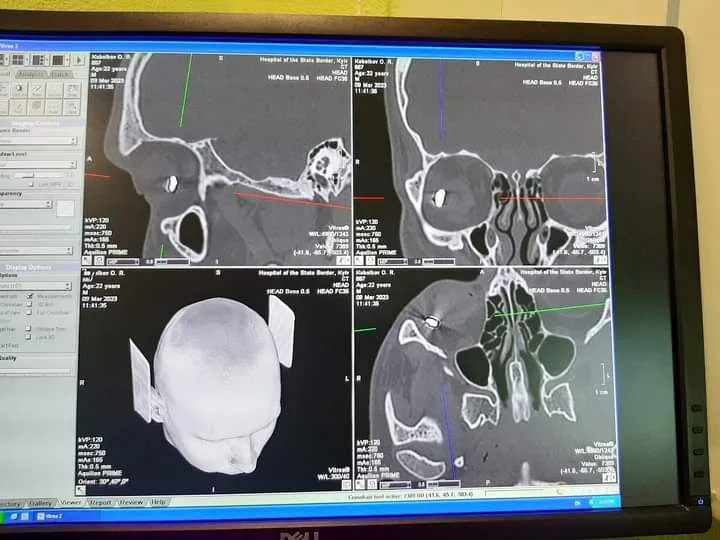

Уламок довжиною близько 1 сантиметра рік пробув в оці прикордонника. Лише нещодавно оборонця Маріуполя вдалося звільнити з російського полону та провести операцію.

Уламок довжиною 1 сантиметр видалили з ока оборонця Маріуполя / Фото Піменової

Уламок пробув в оці прикордонника рік / Фото Піменової